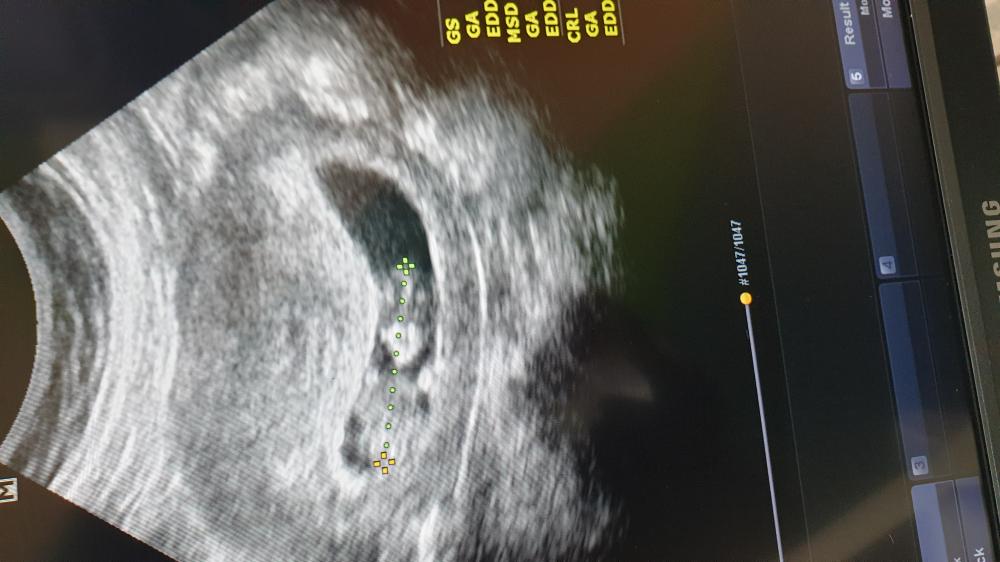

مساء الخير بنات انا عضوه جديده معاكم الاسبوع 12 حسبتي على 10 / 7 الولاده ان شاء الله بس في احتمال ولاده مبكره بس ان شاء الله خير 🌺🤍

على حسب الدوره ولادتي ب١٤ والسونار يعطي ٢٧ استغربت